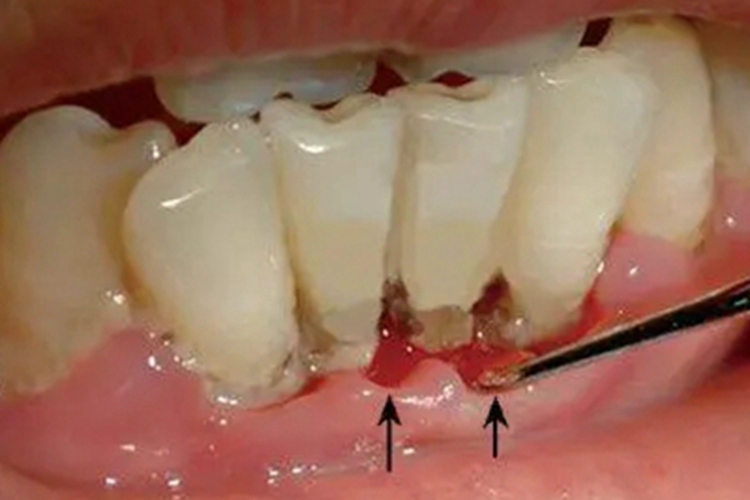

急性坏死性龈口炎部分患者牙龈可出现红肿、渗血、溃疡、糜烂,伴有疼痛。

急性坏死性龈口炎部分患者牙龈可出现红肿、渗血、溃疡、糜烂,伴有疼痛,口内有特殊的坏死性口臭,重症者可出现低热、疲乏等症状,建议尽早就医治疗,以免牙槽骨暴露、骨坏死。

急性坏死性龈口炎需尽早遵医嘱给予抗感染治疗,如早期可刮去坏死组织及大块牙石,使用过氧化氢溶液冲洗;再使用甲硝唑片、维生素C片等药物,还可选择银花、甘草等中药煎水漱口。